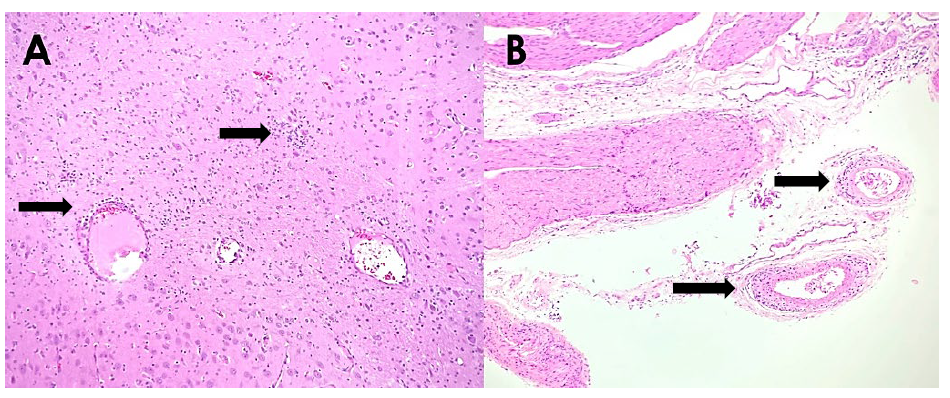

A postmortem submission to the AHL of two 2 to 3-day-old piglets from a herd with a recent history of young piglets with unusual body conformation (pinned-back ears and humped backs) followed by signs of pneumonia and death was recently completed. A diagnosis of PCV3 infection was made by a combination of test results including: suggestive histological lesions, strongly-positive PCR detection of PCV3 in lung tissue, and ISH testing. Histological lesions in both piglets included multi-organ mononuclear perivascular cuffing, and vasculitis within sections of lung, heart, kidney, liver, stomach, intestinal mesentery, brain and spinal cord (Fig. 1). PCR testing of a pooled sample of lung from both pigs was positive for PCV3 with a Ct value of 19.99. A single section of brain with non-suppurative vascular lesions was sent to the Veterinary Diagnostic Laboratory of Iowa State University for ISH testing, and profound intracytoplasmic staining of both neurons and adjacent glia for PCV3 was detected. Although non-suppurative encephalitis in neonates has been documented previously, this was one of the first cases diagnosed at the AHL.

Figure 1. Histological lesions of PCV3 infection in piglets (H&E stain). A. Lymphoplasmacytic encephalitis of the midbrain (arrows). B. Arteries within the leptomeninges of the spinal cord infiltrated or cuffed by plasma cells and lymphocytes (arrows).